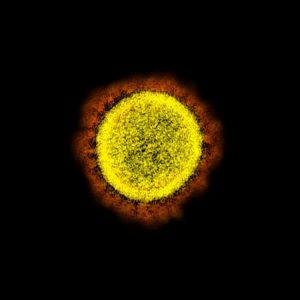

Medikal görselleştirme uzmanları, virüsü sağlıklı hücrelerden ayırmak için renklendirdi. Yapılan çalışmada corona virüsün insan hücrelerinde yarattığı tahribat tüm yönleriyle açığa çıkarıldı. Bilim insanları elektron mikroskobu kullanarak, Covid-19’a neden olan hatayı araştırdılar. Burada bir tarama elektron mikroskobu altında görülen yuvarlak sarı nesneler Covid-19’a neden olan virüsleri gösteriyor.

Diğer bir fotoğrafta ise, virüs partiküllerine adını veren dış kenarındaki sivri uçları açıkça gösteriyor. ‘Corona’ Latince taç veya hale anlamına geliyor.

İşte corona virüsün insan hücrelerinde ilerleyişinden kareler…